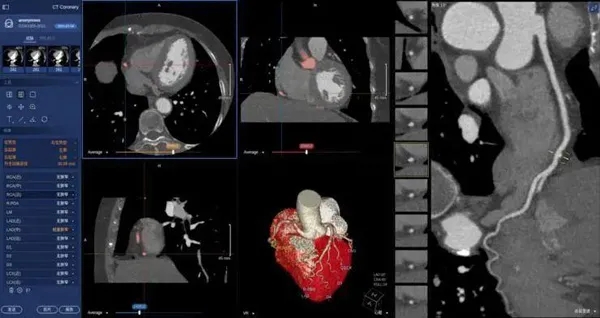

醫(yī)學(xué)視覺檢測

在醫(yī)學(xué)領(lǐng)域,機器視覺主要用于醫(yī)學(xué)輔助診斷。首先采集核磁共振、超聲波、激光、X射線、γ射線等對人體檢查記錄的圖像,再利用數(shù)字圖像處理技術(shù)、信息融合技術(shù)對這些醫(yī)學(xué)圖像進行分析、描述和識別,最后得出相關(guān)信息,對輔助醫(yī)生診斷人體病源大小、形狀和異常,并進行有效治療發(fā)揮了重要的作用。不同醫(yī)學(xué)影像設(shè)備得到的是不同特性的生物組織圖像,如X射線反映的是骨骼組織,核磁共振影像反映的是有機組織圖像,而醫(yī)生往往需要考慮骨骼有機組織的關(guān)系,因而需要利用數(shù)字圖像處理技術(shù)將兩種圖像適當(dāng)?shù)丿B加起來,以便于醫(yī)學(xué)分析。